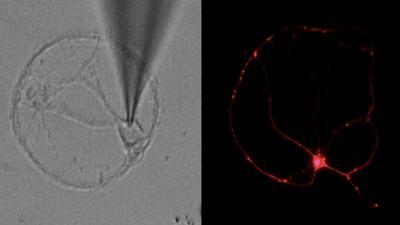

This is a photomicrograph of nerve cell during an electrical recording (left), fluorescently labeled nerve cell (right).

(Photo Credit: Sanford-Burnham Medical Research Institute)